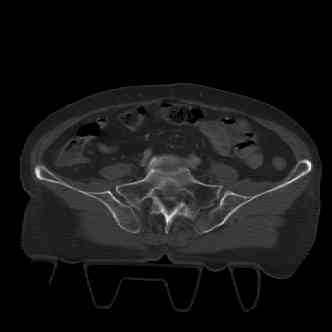

attached are several CT cuts. please let me know if you need more. the CT is pre-pelvic ex-fix placement.